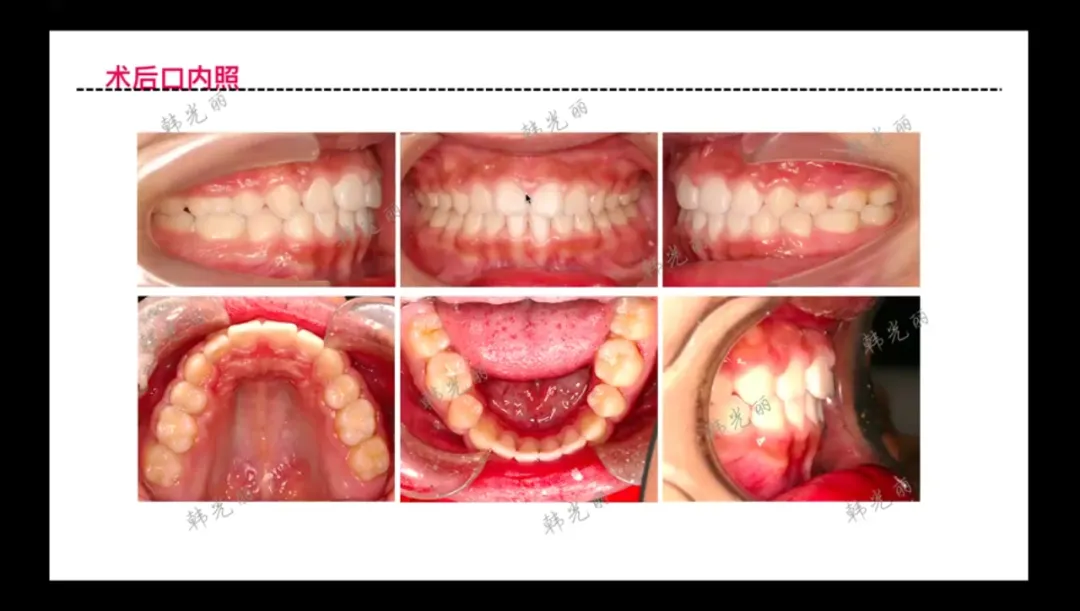

治疗效果评估

• 面部改善

:鼻小柱下方区域(颏部、唇部、唇峰、鼻唇角)获得显著形态改变

• 局限说明

咬合状态

:建立完美的牙合关系,实现功能性咬合与美学效果的统一